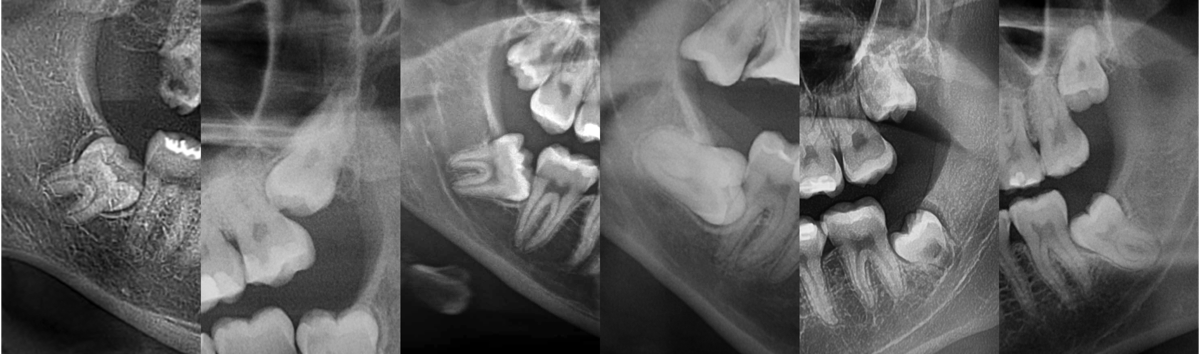

Pacjent 3

Pacjent zgłosił się ze zużytym tymczasowym mostem protetycznym

Zaplanowane leczenie obejmowało wykonanie nowych koron ceramicznych na podbudowie metalowej oraz protez szkieletowych górnej i dolnej.